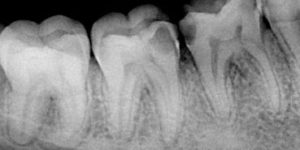

RVG (radiowizjografia) umożliwia wykonywanie ,bez ryzyka, wielu zdjęć wszystkim pacjentom, łącznie z dziećmi. Obraz jest rejestrowany przez specjalny elektroniczny czujnik o niewielkich rozmiarach, który jest umieszczany w jamie ustnej pacjenta w specjalnym trzymadełku. Dzięki wyeliminowaniu kliszy RTG o dużych wymiarach i ostrych krawędziach znacznie łatwiej można wykonać wysokiej jakości zdjęcie u pacjentów z odruchem wymiotnym. Obraz uzyskiwany za pomocą RVG jest w formie cyfrowej, dzięki czemu można poddać go specjalistycznej analizie diagnostycznej, co było niemożliwe w przypadku klasycznych zdjęć RTG na kliszach. Analiza komputerowa umożliwia m.in. wykonanie bezpośrednio na zdjęciu pomiarów odległości, kątów, gęstości oraz płynną regulację parametrów ekspozycji zdjęcia (kolor, kontrast, jasność, nasycenie).